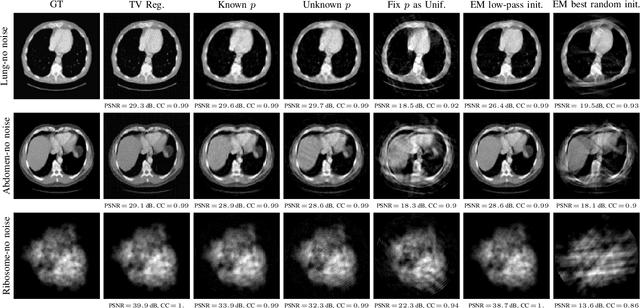

Abstract:Unknown-view tomography (UVT) reconstructs a 3D density map from its 2D projections at unknown, random orientations. A line of work starting with Kam (1980) employs the method of moments (MoM) with rotation-invariant Fourier features to solve UVT in the frequency domain, assuming that the orientations are uniformly distributed. This line of work includes the recent orthogonal matrix retrieval (OMR) approaches based on matrix factorization, which, while elegant, either require side information about the density that is not available, or fail to be sufficiently robust. In order for OMR to break free from those restrictions, we propose to jointly recover the density map and the orthogonal matrices by requiring that they be mutually consistent. We regularize the resulting non-convex optimization problem by a denoised reference projection and a nonnegativity constraint. This is enabled by the new closed-form expressions for spatial autocorrelation features. Further, we design an easy-to-compute initial density map which effectively mitigates the non-convexity of the reconstruction problem. Experimental results show that the proposed OMR with spatial consensus is more robust and performs significantly better than the previous state-of-the-art OMR approach in the typical low-SNR scenario of 3D UVT.